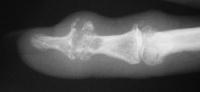

Distal interphalangeal erosive osteoarthritis severe enough that the diagnosis of giant cell or other tumor was suspected. Fortunately, no tumor was encountered at surgery.

These two cases illustrate the use of the Ascension PIP joint implant arthroplasty in the DIP joint position. The stem of the distal component is too wide to fit into the typical distal phalanx, but the proximal component stem will, and in selected cases, the implant will fit in this position if it is placed in a reversed proximal-distal position. These cases illustrate this technique - not as an endorsement, but as a demonstration of  technical feasibility. At one year, each  reconstructed joint was painless and had about 30 degrees range of motion.